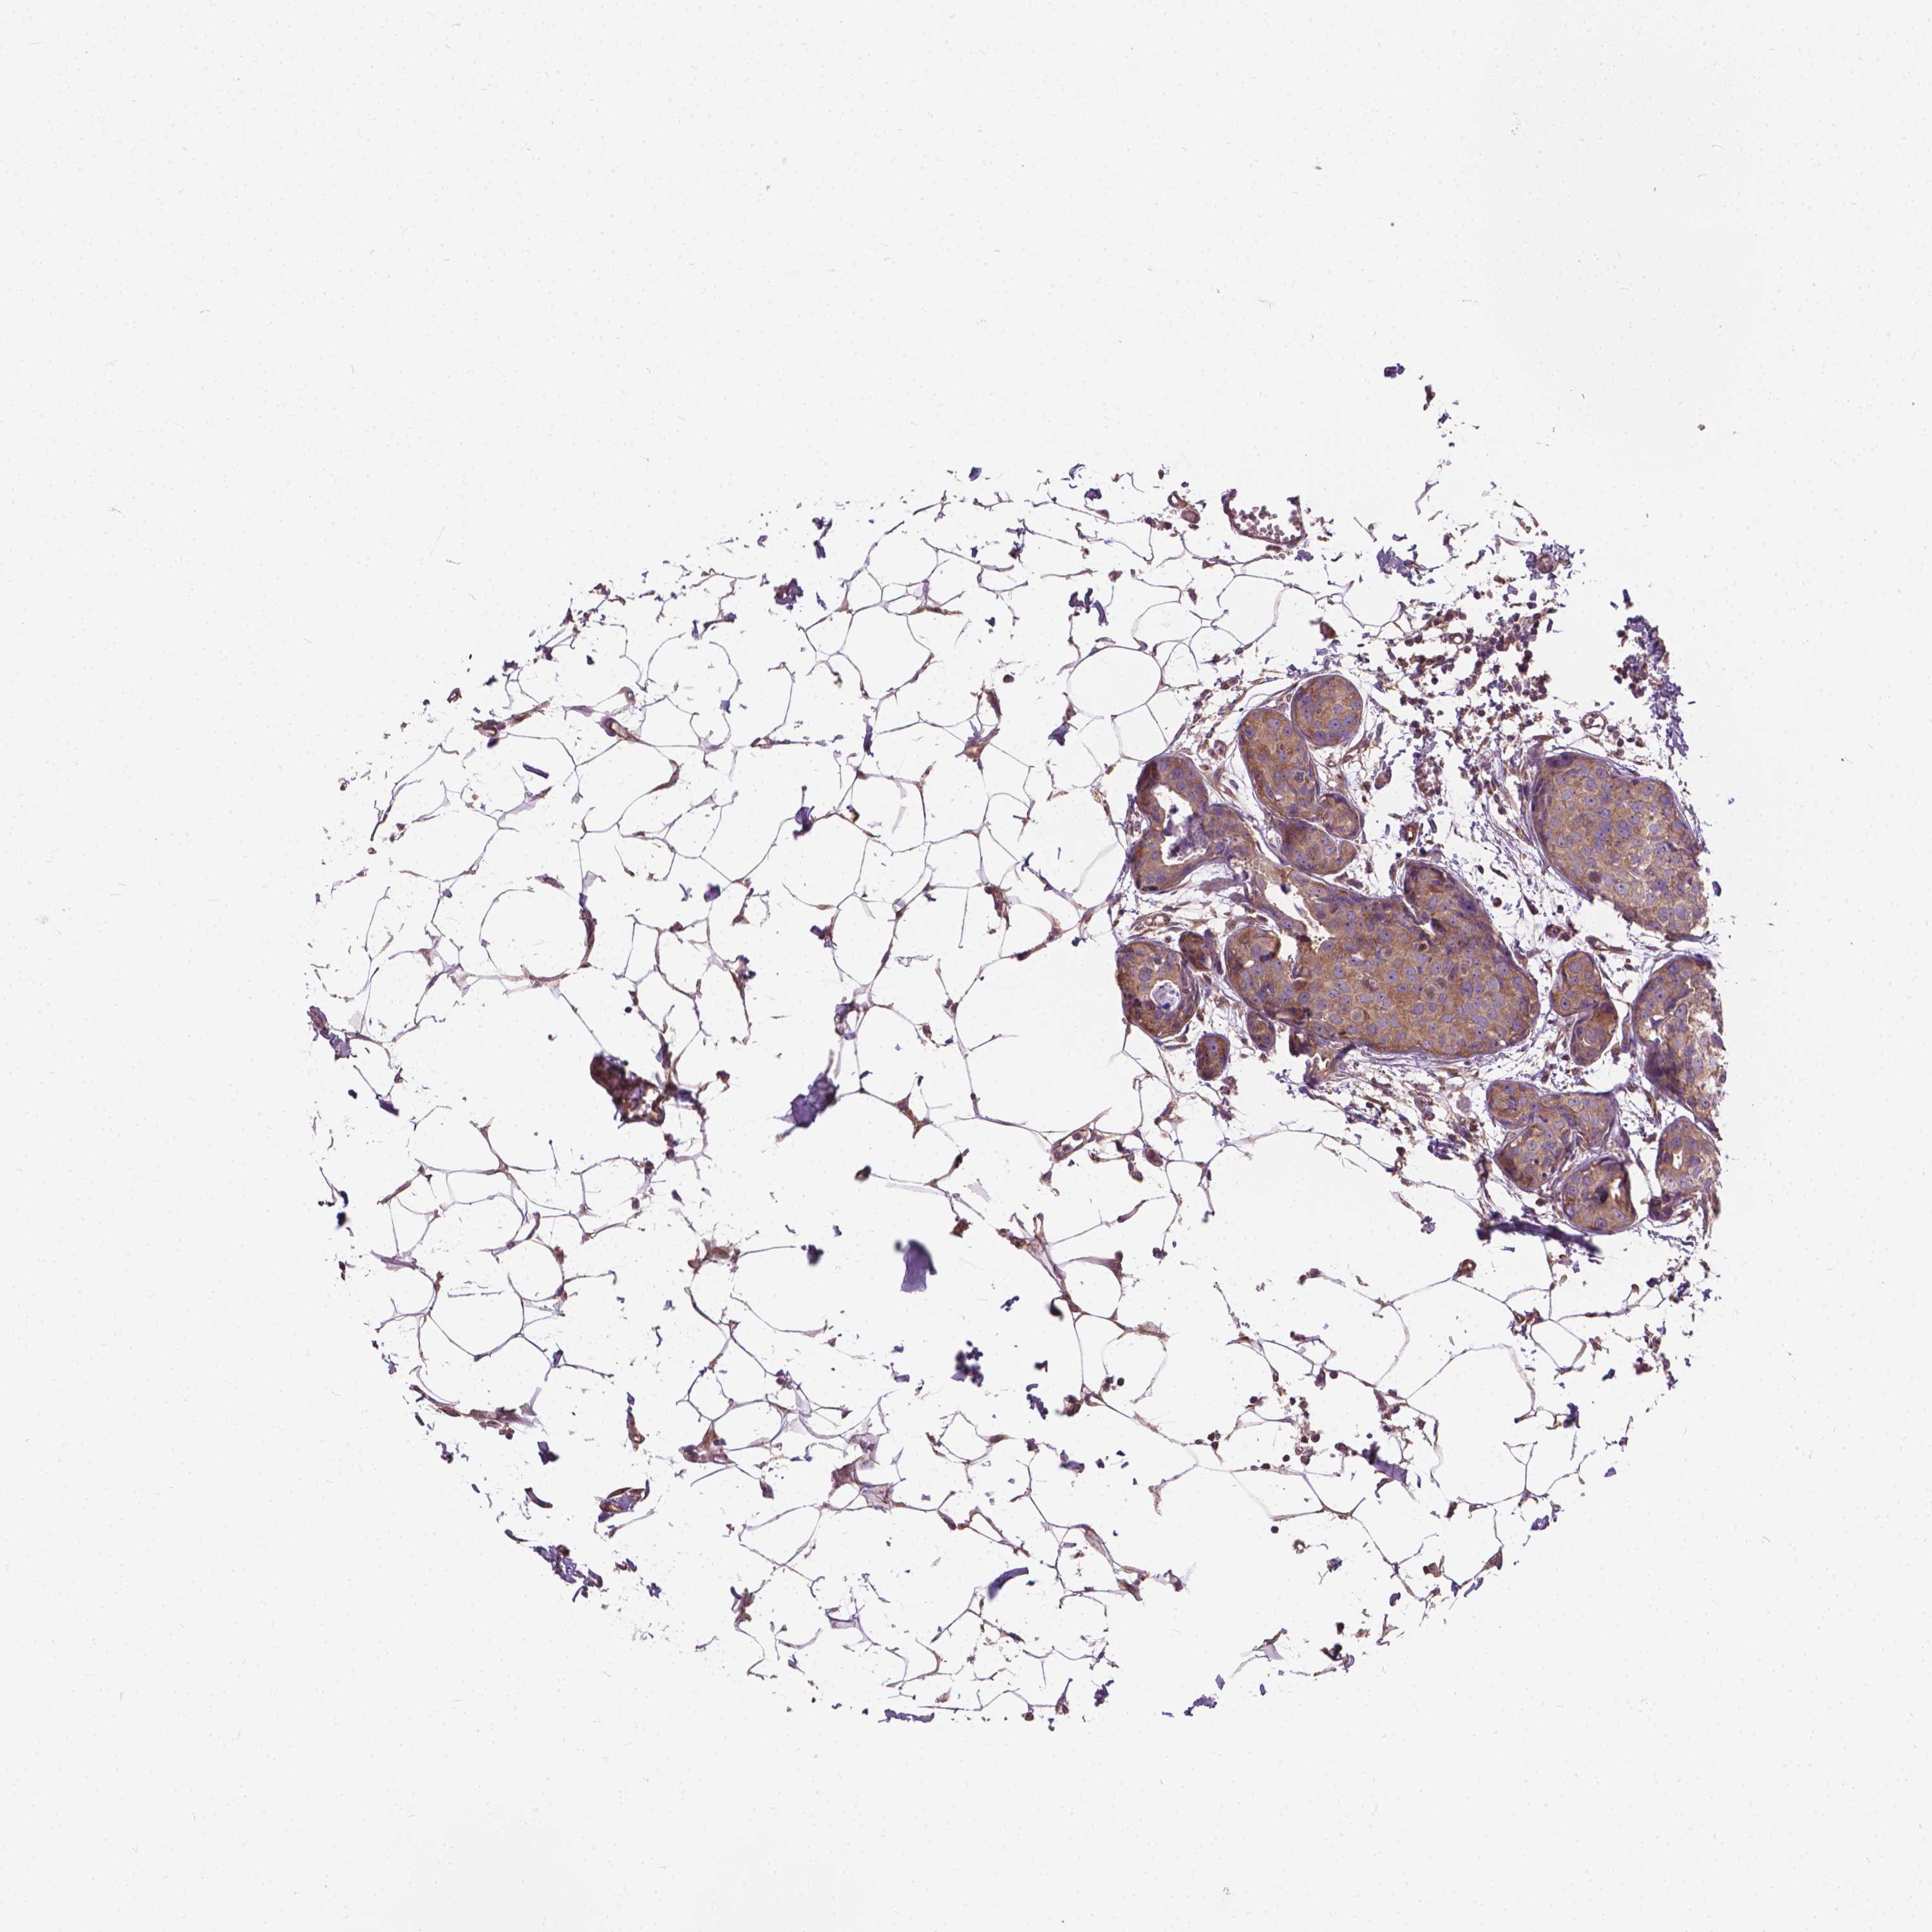

BRCA TCGA BRCA VALIDATION PROTEIN EXPRESSION

ANTIBODIES

AND

VALIDATION